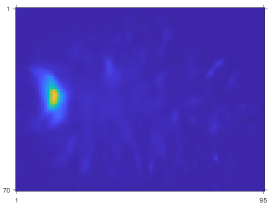

Fig. 9 compares the reconstruction quality between OSEM and CNN-regularized EM algorithm using sequential training, gradient truncation and end-to-end training. Visually, the end-to-end training reconstruction yields the closest estimate to the true activity. This is also evident through the line profiles (subfigure (m) and (n)) across the tumor and the liver.

Refer to caption

Figure 9: Qualitative comparison of different training methods and OSEM tested on Y90superscriptY90{}^{90}\mathrm{Y} VP phantoms. Subfigure (a)-(f) and (g)-(l) show two slices from two testing phantoms. Subfigure (m) and (n) correspond to line profiles in (a) and (g), respectively.

Table III reports the mean activity error (MAE) and NRMSE for lesions and organs across all testing phantoms. Similar to the qualitative assessment (Fig. 9), the end-to-end training also produced lower errors consistently across all testing lesions and organs. For instance, compared to sequential training/gradient truncation, the end-to-end training relatively reduced MAE on average by 8.7%/7.2%, 18.5%/11.0% and 24.7%/16.1% for lesion, healthy liver and lung, respectively. The NRMSE was also relatively reduced by 6.1%/3.8%, 7.2%/4.1% and 6.1%/3.0% for lesion, healthy liver and lung, respectively. All learning-based methods consistently had lower errors than the OSEM method.